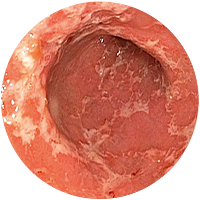

진행성대장암

-